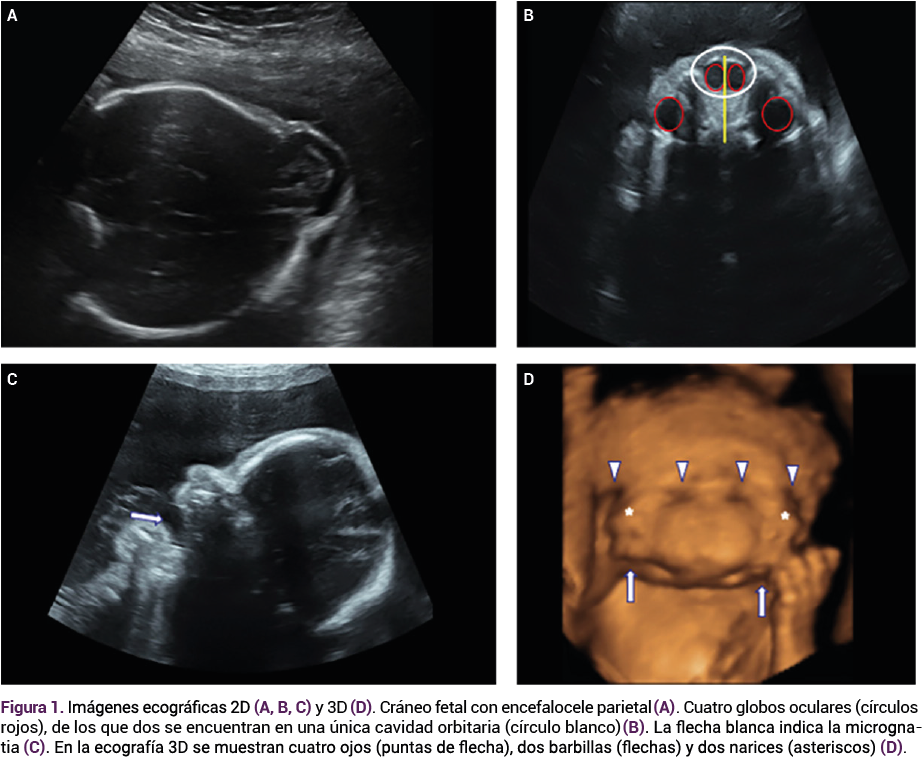

La resonancia magnética fetal reveló, además de la duplicación facial, dos tejidos parenquimatosos cerebrales distintos, junto con agenesia del cuerpo calloso, encefalocele y dilatación de los ventrículos laterales posteriores. La tomografía computada, sin contraste, confirmó los hallazgos. El cariotipo fetal fue normal (46 XY) en la amniocentesis y no se identificaron deleciones, duplicaciones ni variantes en el microarray ni en el panel de secuenciación de nueva generación para anomalías faciales.

<strong>Figura 2</strong>

Figura 2. Imágenes por resonancia magnética fetal y tomografía computada que documentan duplicación cerebral y alteraciones mayores del sistema nervioso central.

El tamiz prenatal, con ecografía bidimensional y tridimensional, puede detectar las malformaciones craneofaciales.15 En muchos casos, una exploración dirigida requiere de otras técnicas adicionales que permitan mejorar la precisión del diagnóstico por ultrasonido.15 En el caso aquí comunicado, el diagnóstico prenatal de duplicación facial completa y encefalocele se estableció con base en una ecografía bidimensional y la ecografía 3D facilitó un examen detallado de los rasgos faciales, lo que finalmente confirmó el diagnóstico de diprosopus.15 Las imágenes de la ecografía 3D también desempeñaron un papel decisivo en la ayuda a la paciente y su familia para comprender la naturaleza compleja de esta malformación.15 Garel y su grupo reportaron la importancia de las técnicas adicionales: la resonancia magnética como método complementario en la evaluación de las afecciones craneofaciales, que destacan la mejor visualización de las estructuras, la ausencia de radiación ionizante y la calidad de las imágenes a pesar de la obesidad de la madre o la cantidad de líquido amniótico.15 Esos mismos autores reportan la importancia de la tomografía computada, teniendo en cuenta el principio ALARA en la aplicación de bajas dosis de radiación.15 Para el estudio del caso aquí comunicado, la resonancia magnética fetal aportó información valiosa del sistema nervioso central al demostrar la duplicación cerebral y la agenesia del cuerpo calloso.15 A pesar de haberse diagnosticado al finalizar el segundo trimestre, la combinación de la ecografía detallada y la resonancia magnética proporcionó información prenatal precisa.15 Esto guió la elección de la paciente con respecto al control del embarazo y permitió a la familia y a los médicos implementar un plan de parto integral.15